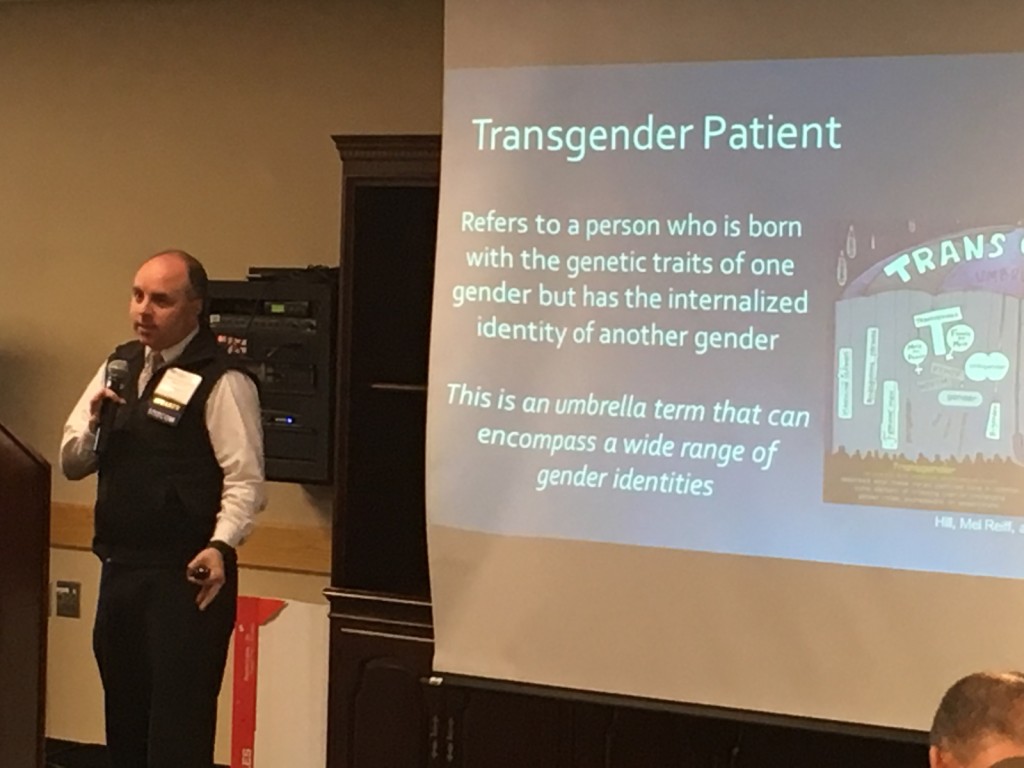

The timing of this year’s CME/Alumni Weekend, held on UNE COM’s Biddeford campus, was á propos. Nestled between Coming Out Day on October 11 and Transgender Awareness Month in November, this year’s CME event featured a UNE COM alumnus who spoke on the timely topic of Transgender Medicine in Primary Care.

On the afternoon of October 21, 2017, the crowd waited patiently to hear John-Paul Bettencourt, D.O. ’12 speak. Dr. Bettencourt has worked at Fenway Health in Boston since 2015 where he specializes in primary care, LGBT and HIV/AIDS medicine. If you haven’t had the opportunity to meet Dr. Bettencourt or heard him present, then you are missing out on a wealth of knowledge and humorous entertainment. From his small frame exudes a dynamic and witty personality, making his lecture on transgender medicine both accessible and engaging to an audience consisting mostly of primary care providers with admittedly limited knowledge of transgender health.

Transgender refers to a person who is born with the genetic traits of one gender but has the internalized identity of another gender. Cisgender, on the other hand, is a term used for a person whose genetic traits and internalized gender are the same.1 Historically, the transgender community has been victimized by discrimination and healthcare has been no exception. People who identify as transgender, or fall under the general umbrella term, have been denied access to medical treatments, and consistently struggle to find physicians who will provide them with regular care.2 According to a recent study, the lack of services and overall physician willingness to treat members of the transgender community may be partially due to a lack of knowledge and understanding of transgender medicine itself.2 This is not to diminish the discrimination that transgender people experience, but to acknowledge that the lack of preparedness for physicians may be one reason for healthcare disparities within the community. The article, “Making Primary Care Trans-Friendly” echoes the belief that physicians are generally afraid to offend their patients who are transgender, and are concerned that their lack of knowledge of hormone therapy could inadvertently harm them.3

In his presentation, Dr. Bettencourt spoke to the team approach that his office embraces. It isn’t solely a one-on-one relationship between doctor and patient, but a team of people that includes a nurse, patient advocate, behavioral health specialist, case manager, and available support groups to meet the needs of their transgender patients.4 This is one model that pulls together various resources in order to best care for their transgender population. It goes without saying that rural areas don’t have the resources that a city such as Boston, or even Portland, have more readily available. Because of this, Dr. Bettencourt consults with other primary care physicians who want to give their transgender patients the care they need, wherever they are in their process and geographically.5

Echoed in Dr. Bettencourt’s presentation was the idea that transgender medicine is not specialty medicine, but falls under primary care.4 However, there is a definite need for education on transgender health in order to provide physicians with the knowledge necessary to feel competent in their ability to treat members of the community. Practicing physicians are already required to earn continuing education credits for licensing in order to ensure they are on the cutting edge of medical treatments and interventions. For example, since more physicians have seen an increase in patients addicted to opioids, some states such as Massachusetts require opioid education for physician licensing.6 Similarly, the first step to the advancement of transgender medicine is within the scope and ability of primary care. Physicians have access to the tools necessary to treat their transgender patients, but what is missing is the knowledge of where to seek out those resources, and the impetus to do so.

Isabel Lowell, M.D., a professor at Emory University School of Medicine, Department of Family and Preventative Care, believes that “Making [transgender care] primary care just means that any transgender patients anywhere in the country can go to their own doctor.”3 Similarly, Dr. Bettencourt quotes A.T. Stills in his presentation: “To find health should be the object of the doctor. Anyone can find disease.”4 The osteopathic principles instruct D.O.s to treat the mind, body and spirit. In his lecture, Dr. Bettencourt states that his treatment goal is to lessen the gender dysphoria in his transgender patients, or, in short, to unite mind, body, and spirit. In terms of treatment, he states, “I treat the patient, not the numbers.” Despite what resulting labs or other diagnostic tools tell him, listening to his patients is key to understanding what direction or what avenue he will inevitably choose to pursue.4 The 2007 Virginia Trans Health Initiative Survey found that 60% of transwomen and 23% of transmen have at one time or another taken self-prescribed hormones, therefore, the role of the primary care provider is to regulate and monitor their patients’ levels in a controlled environment.4